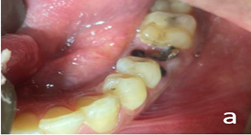

- #26, #36 – Root piece (Figure 2a and 2b)

Figure 2a: Before treatment clinical photograph #36